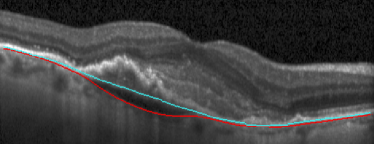

(a) Before TPS

(b) After TPS

II-C Post-processing with thin plate splines

We use a thin plate spline (TPS) [37] interpolation on the volumetric 3D OCT scan to estimate a viable position of the BM in the uncertain areas. The TPS finds an interpolating surface with a set of control points to assure minimum bending of the BM. With TPS, we replace the uncertain BM positions with their interpolated values.